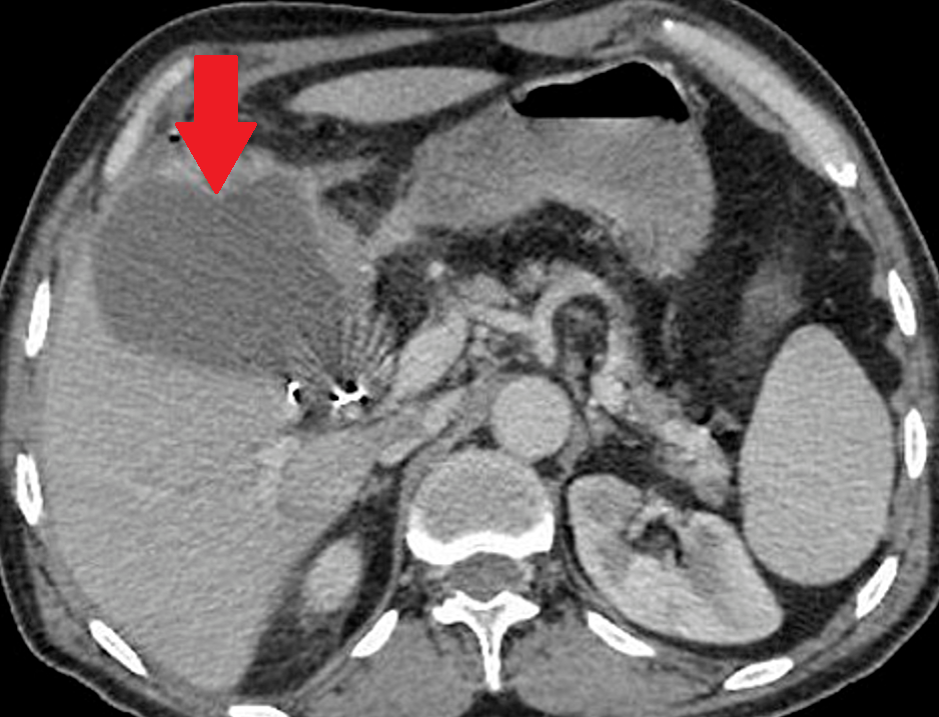

Abdominal CT scan. Hemorrhagic rupture of a simple hepatic cyst without active hemorrhage. The presence of free intraperitoneal fluid is noted (Courtesy Dr. V. Penopoulos)